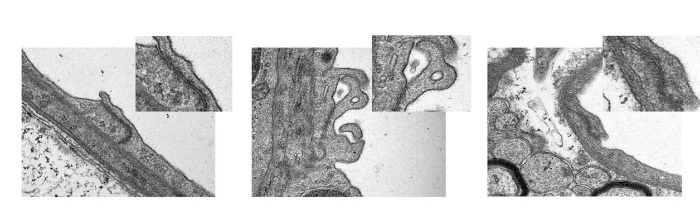

На трансмиссионной электронной микроскопии видны нарушения плотных контактов у SS мышей (2-ая фотография)